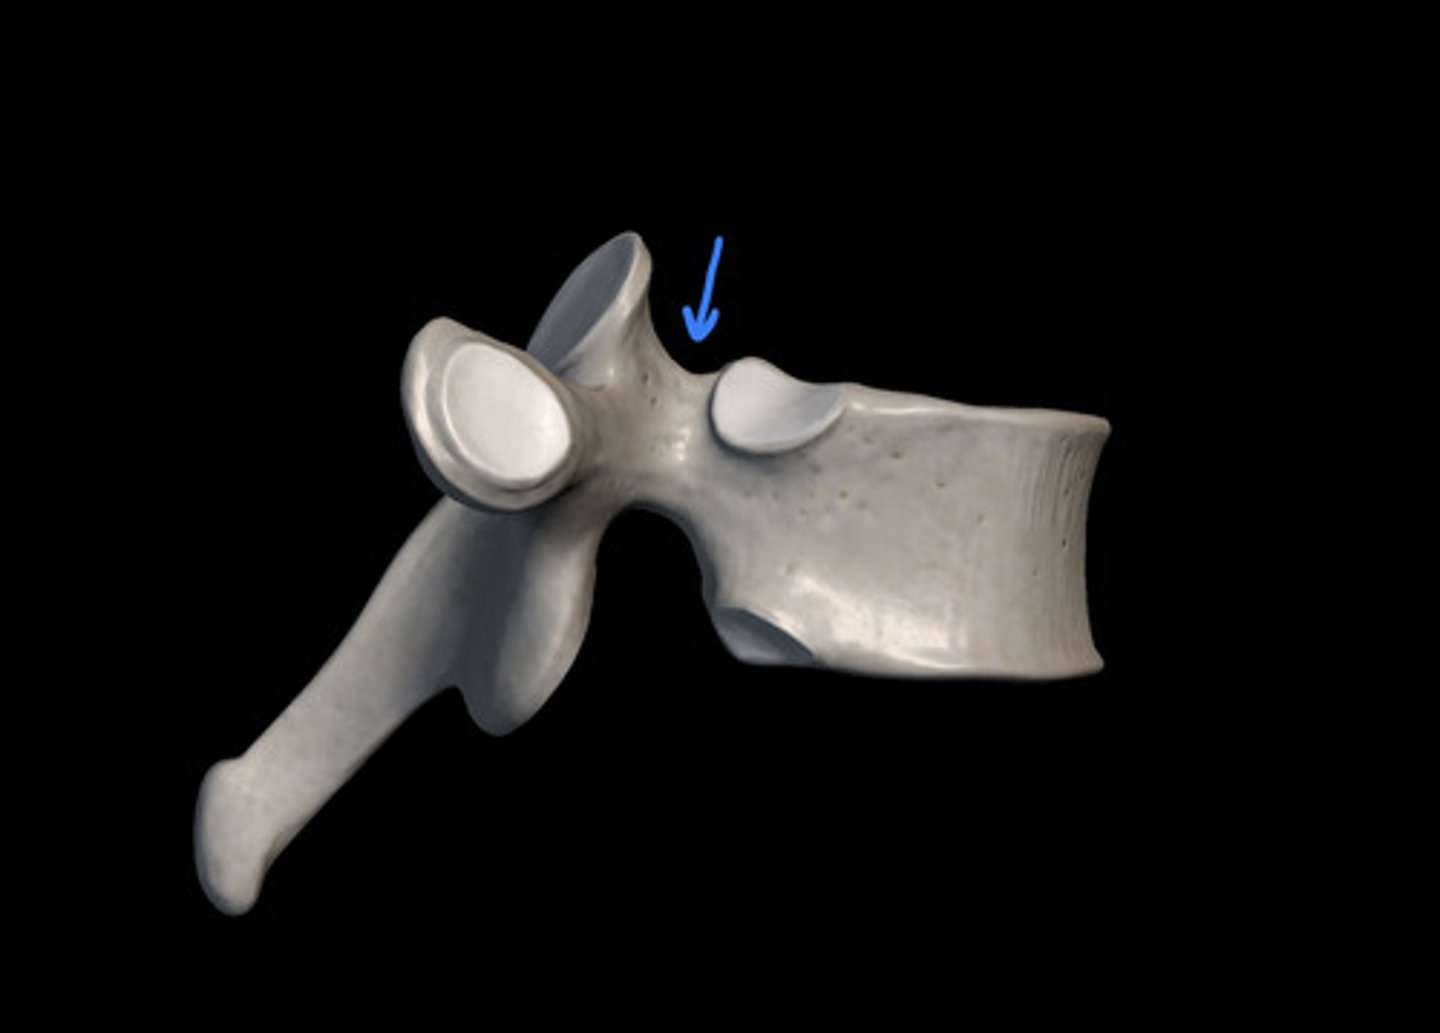

transverse costal facet

rib articulation (attachment) ONLY FOUND IN T1-T12

what is the purpose of the transverse costal facets

transverse costal facets (articulations) where ribs attach to

what differenciates the T spine vertebra